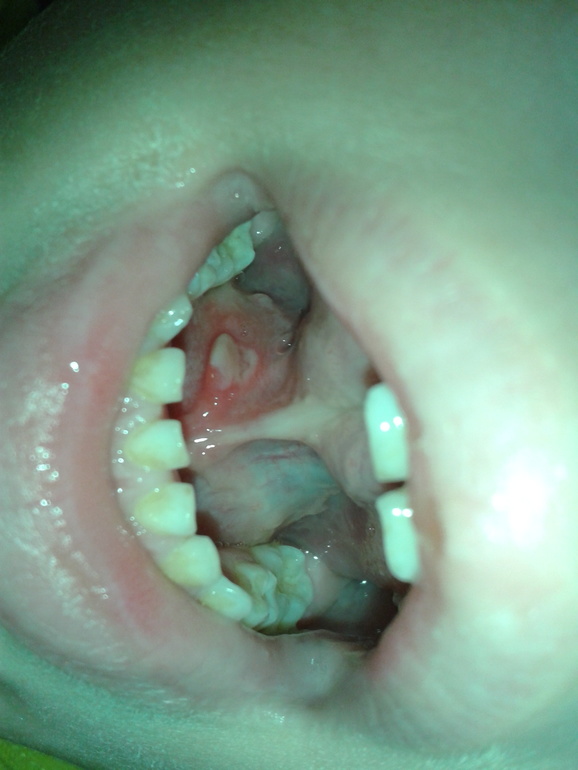

Новообразование на слизистой под языком

Добрый день, Алина Владимировна! У ребенка (5лет) под языком появилось продольное образование, как будто второй язычок, потом, скорей всего, при чистке зубов задели щеткой, образовалась язвочка, сейчас все это воспалилось, покраснело, болит, ребенку больно поднимать язык. С января до конца марта занимались у логопеда, под языком все чисто было, заметила примерно неделю назад, не знаю, связано ли это. Подскажите, пожалуйста, что это, чем лучше обрабатывать пока и к какому врачу бежать: стоматологу или хирургу?

И это больше похоже не на образование, а на последствие травмы.

Зачем к хирургу тогда? Он проконсультирует и обработает данное место. И так же даст консультацию по короткой уздечки языка, т.к. занятие с логопедом не принесут желаемого результата. Уздечка короткая и массивная. И ее присутствие будет портить стоматологическую картину в будущем ( может сказаться на формирование прикуса, на оголение шеек нижних центральных резцов...)

Необходима пластика уздечки языка с последующим занятием у логопеда.